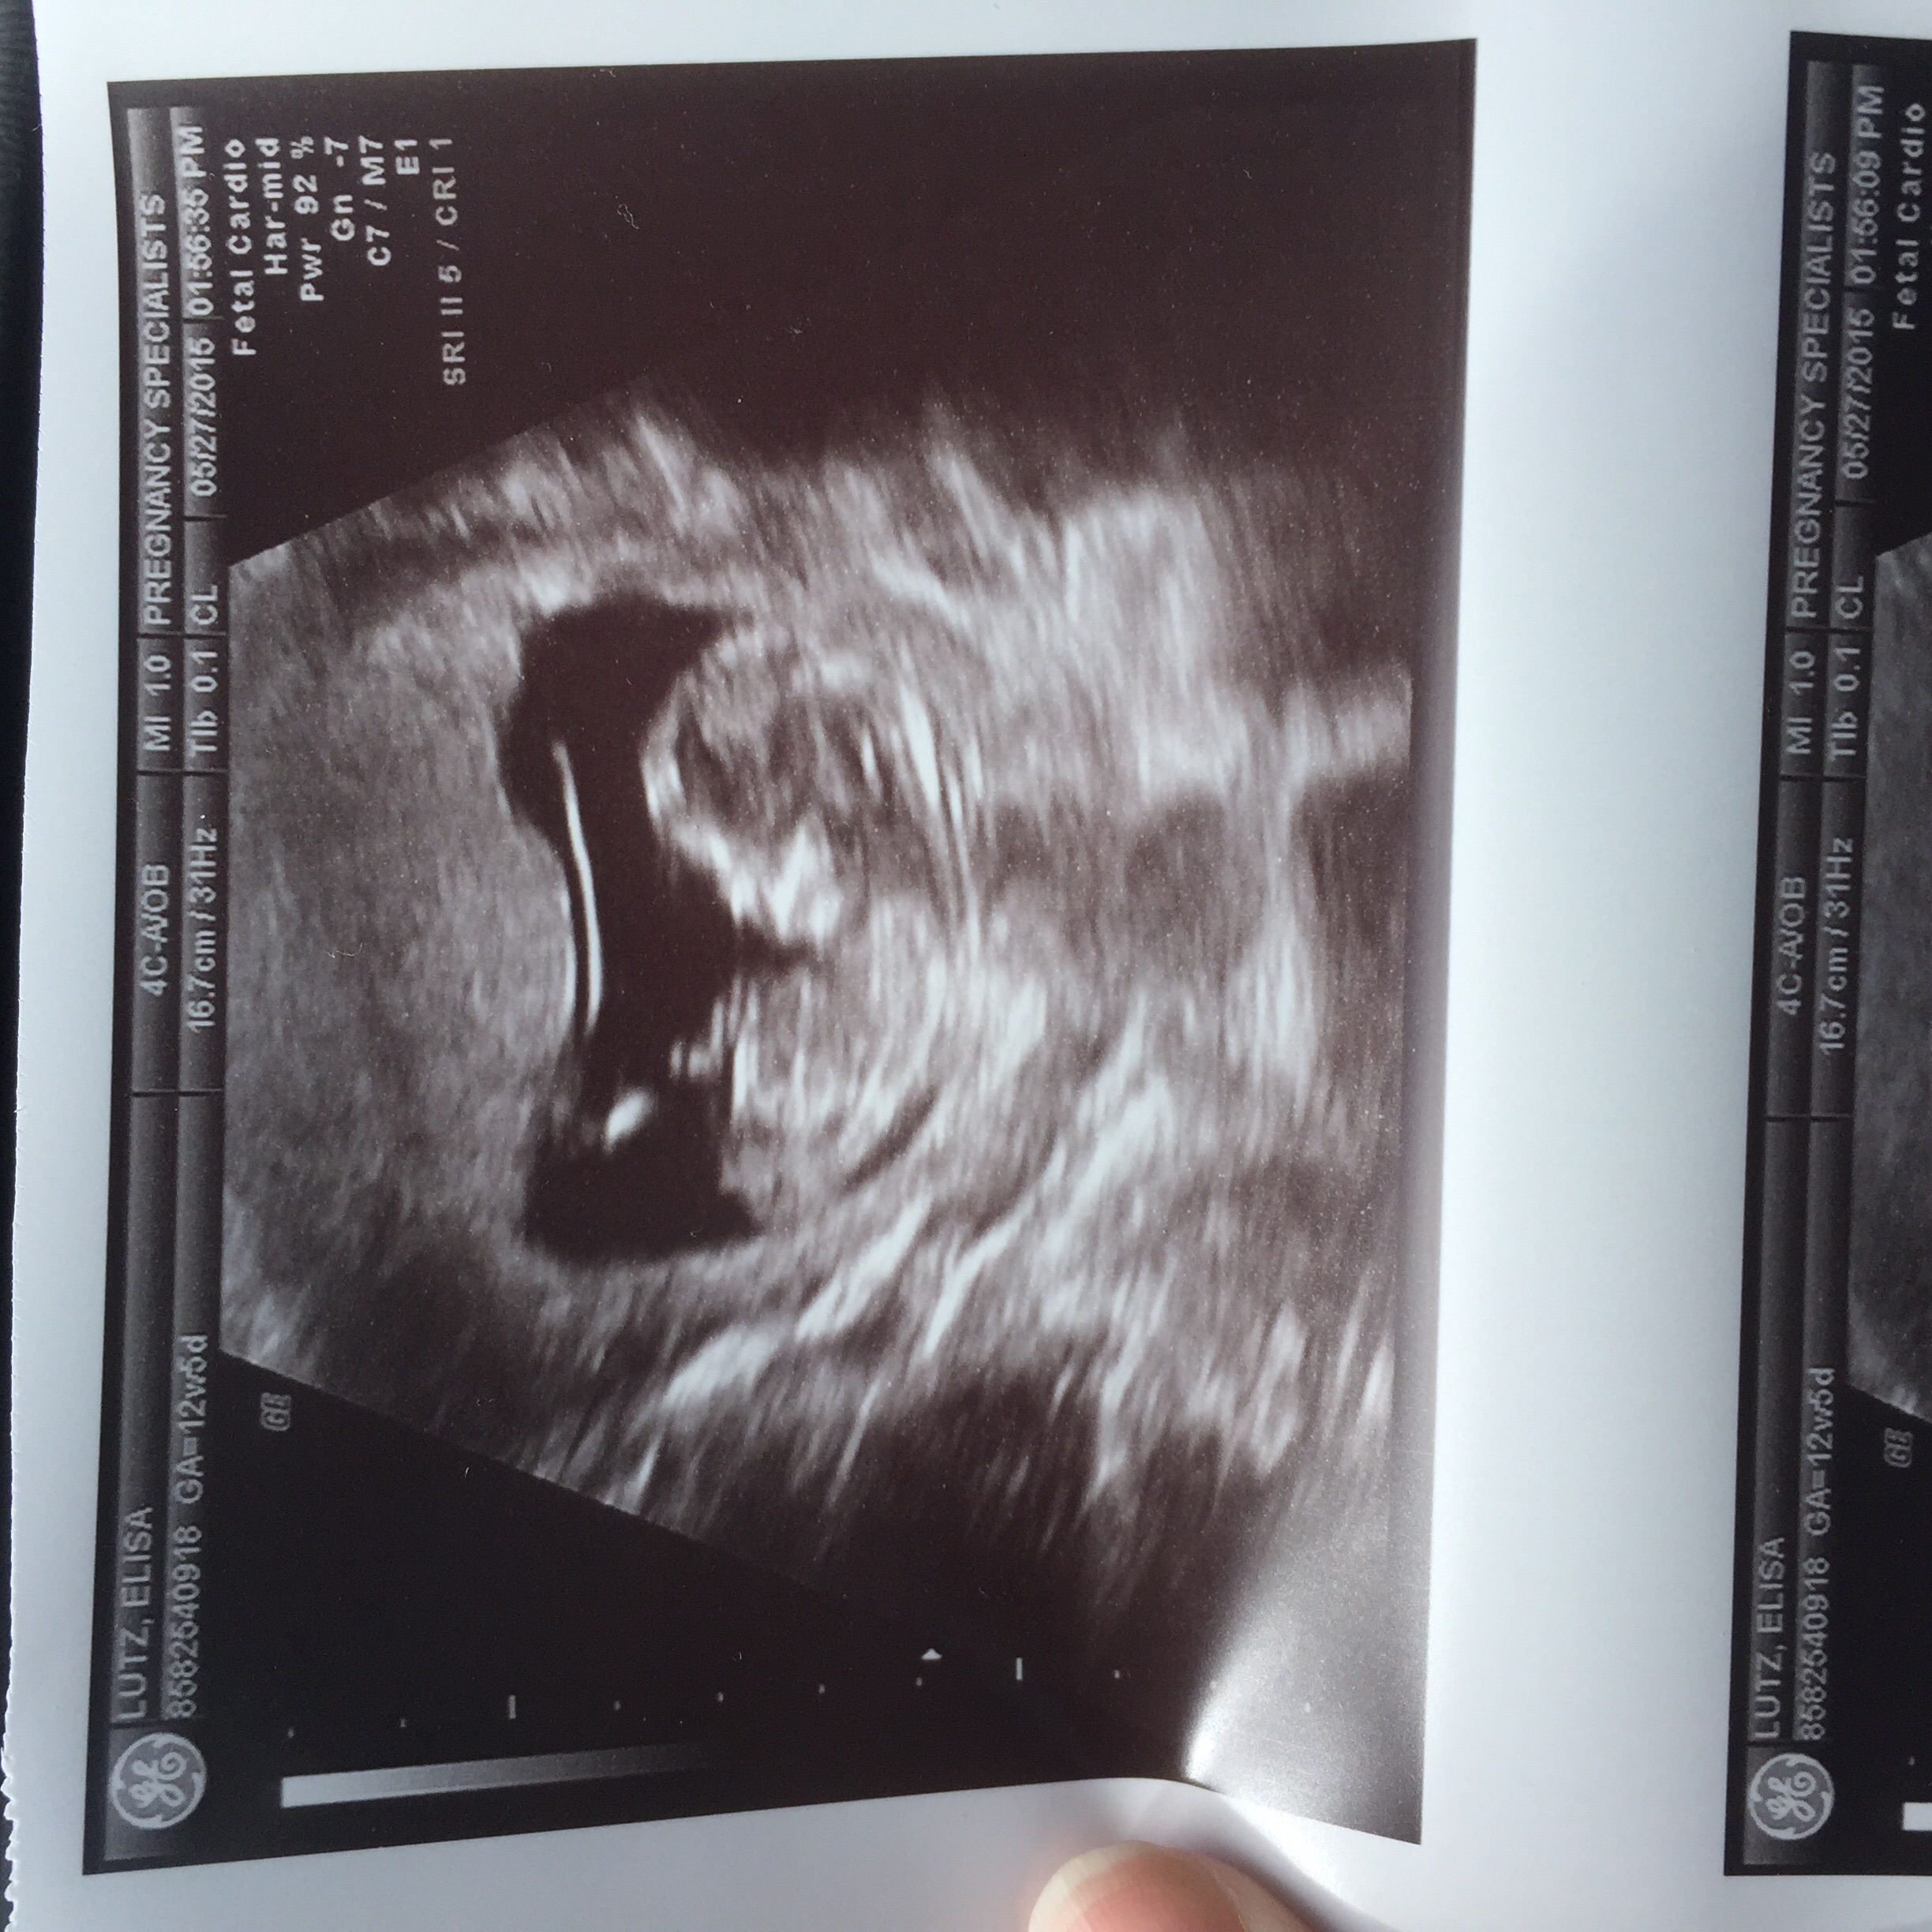

I already knew we were having a boy from the MaterniT21 blood test but we could clearly see the penis on today's ultrasound (12 weeks 3 days).

There IS a "nub theory" some techs swear by. Depending on the angle of the nub (above 30 degrees means boy, I think) you can sometimes determine the gender but obviously it's not 100% accurate

According to the nub theory it does have an angle so we are probably having a boy.